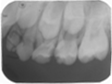

65MO深大龋洞,色棕黄,质软,叩痛(+),不松动,牙龈红肿,未见瘘管。 X线片示:冠部低密度影达髓腔,根分歧区大面积低密度影,近远中根内侧壁见吸收。25牙胚存,未拍全。 64MO深大龋洞,色棕黄,质软,叩痛(+),不松动,牙龈略红肿。 X线片示:根分歧区密度减低。 84OD深大龋洞,色棕黄,质软,叩痛(-),不松动, 85MO牙色充填体周围见龋坏,色黑,质软,叩痛(±),不松动,龈无异常。 X线片示:根周见低密度影,44,45牙胚存,未拍全。 54DOL深大龋洞,色黑,质软,叩痛(-),不松动, 55O窝沟色黑,卡探针,叩痛(-),不松动,龈无异常。 74OD,75MO半年前曾于外院行充填治疗,现检查见充填体边缘色黑,卡探针,充填体略有松动。

诊断:64,65,84,85慢性根尖周炎;54DOL深龋,55O中龋;74OD,75MO继发深龋 处置:64,65,84,85根管治疗 54DOL,55O行充填治疗 74OD,75MO去除旧充填体后充填治疗